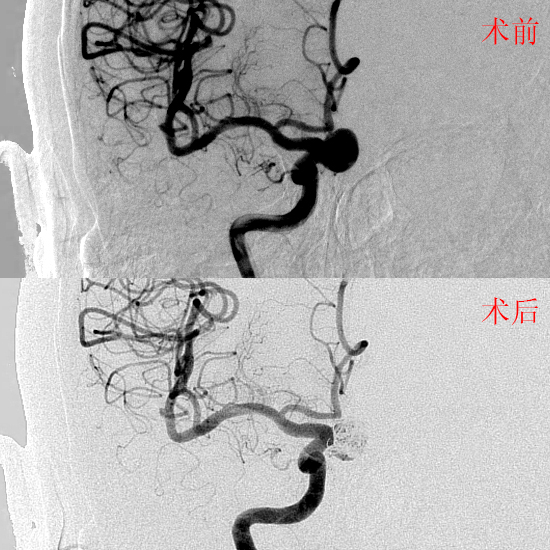

医生说问题不在眼睛,而是在“眼睛后面那段大血管上鼓了个包”。这就是我们常说的颅内动脉瘤。片子显示:一个12.3×11.5×5.1mm的球形动脉瘤处在右侧颈内动脉的眼段——通俗讲,就是供眼睛和大脑前部的那根主干血管上,拐弯处顶了个包。这样的包如果破了,容易颅内出血,所以医生建议尽快处理。

手术那天,医生先把微型弹簧圈填进鼓包,让血液不再流近动脉瘤,然后在主干血管里再“搭一道栅栏”(血流导向密网支架),让血流不再冲向鼓包,慢慢把它“晒干”。术后造影看,鼓包基本不再显影,主干血流通畅。